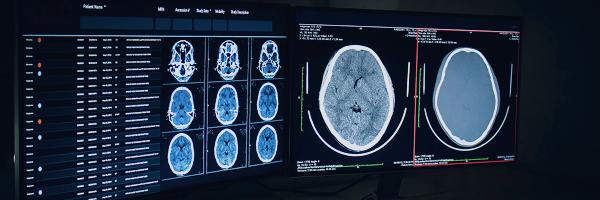

AI-drevne verktøy for medisinsk bildebehandlingtolke røntgenbilder, MR- og CT-skanningerDe forbedrer diagnostisk nøyaktighet og fremskynder prosesser. Disse løsningene hjelper radiologer med å oppdage potensielle problemer tidligere, ettersom de automatisk fremhever abnormiteter, som svulster, brudd eller beinsporer. For SimonMed, en leverandør av medisinsk bildebehandling, bidro AI-verktøy for radiologi til ågenerere funnrapporter 82% raskere.